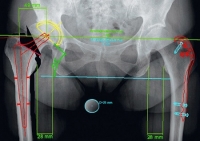

Phần mềm MediCAD 2D cho phép các bác sĩ chuyên khoa đánh giá tình trạng biến dạng xương và khớp, đồng thời lập kế hoạch phẫu thuật thay khớp và chỉnh hình xương dựa trên hình ảnh X-quang 2D.